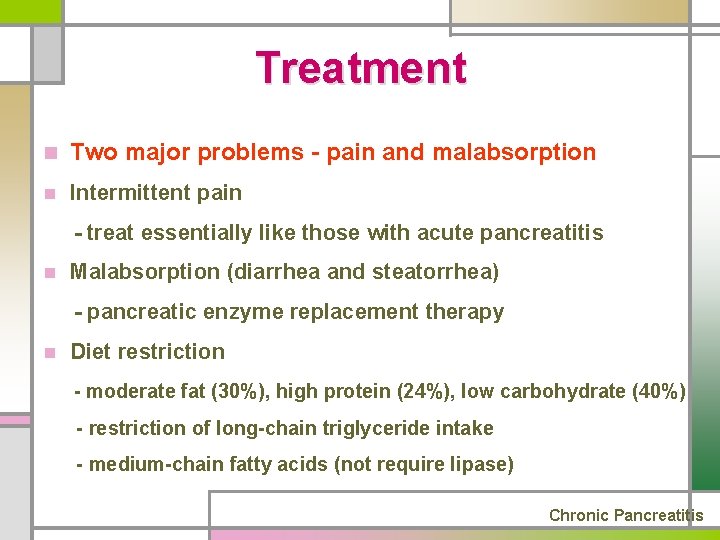

Treatment n Two major problems - pain and malabsorption n Intermittent pain - treat essentially like those with acute pancreatitis n Malabsorption (diarrhea and steatorrhea) - pancreatic enzyme replacement therapy n Diet restriction - moderate fat (30%), high protein (24%), low carbohydrate (40%) - restriction of long-chain triglyceride intake - medium-chain fatty acids (not require lipase) Chronic Pancreatitis

Severe and persistent pain n Avoid alcohol & avoid large meals rich in fat n Narcotics n Administration of pancreatic enzymes (75% effect) - effective in mild to moderate exocrine dysfunction - H 2 RA, proton pump inhibitors are effective n Octreotide n Endoscopic treatment n Splanchnicectomy, celiac ganglionectomy n Surgical procedures Chronic Pancreatitis